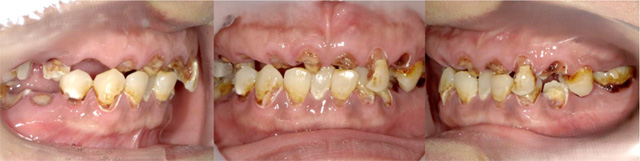

オールオン4の治療例:1

治療前

治療後